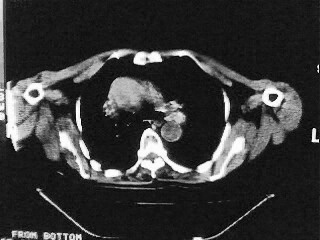

女,79,咳 嗽月余,无其它不适

(1)食管裂孔疝(2)贲门失弛缓症。建议行上消化道钡餐检查。

后纵隔内左心房至肝左叶后方椎体中线偏左巨大软组织包块,其壁均匀比较薄,其内可见宽气液平。

考虑食管裂孔疝。建议钡餐检查